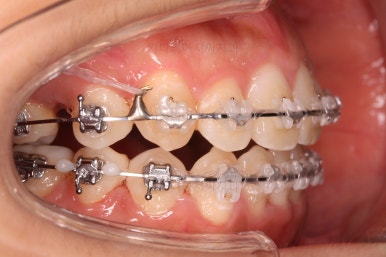

초진 시 입안의 모습입니다.

그냥 봐도 뭔가 애매함이 있죠?

중앙선이 맞지 않고, 교합이 떠보이는 양상이네요.

윗니는 좌측 작은 어금니가 한 개 모자랐고 아랫니는 앞니 하나가 모자라네요.

그런데 앞니는 아랫니가 1개 모자란 채로 교합이 맞춰져서 윗니가 하나 부족한 채로 애매한 상태였어요.